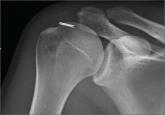

ArticleOrthopedic Management of Complications of Using Intraosseous CathetersAuthor:Barlow BPublish date: April 1, 2014 Intraosseous (IO) catheters have been used for vascular access in trauma and critically ill patients with increasing frequency in emergency depart...Read More